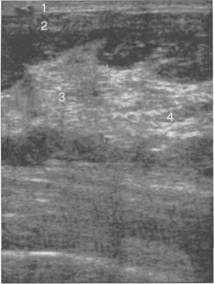

Рис. 10.34. Репродуктивный УЗ-тип строения молочной железы.

Пациентка Н., 28 лет.

1 — кожа; 2 — подкожная жировая клетчатка; 3 — фиброгландуляр-

ная ткань средней эхогенности; 4 — единичная жировая долька.

Кожа визуализируется как тонкая гиперэхогенная линия толщиной 0,5—2,0 мм. Подкож­ная жировая клетчатка лоцируется в виде единичных жировых долек или в виде единого пла­ста жировой ткани гипоэхогенной структуры.

С увеличением возраста и количества беременностей имеет место жировая трансформа­ция железистой ткани, поэтому железистая часть молочной железы визуализируется в виде единого пласта средней эхогенности, на фоне которого определяются гипоэхогенные округ­лые скопления жировой ткани. Чем больше срок, прошедший со времени первой беременно­сти, тем более выражены явления жировой трансформации железистой ткани. Во вторую фазу менструального цикла на фоне железистой ткани появляется изображение расширенных ги-поэхогенных млечных протоков.

Передний контур паренхимы железы — волнистый за счет выпячиваний в местах прикрепления связок Купера. Соединительнотканные структуры умеренно дифференцируются (рис. 10.34).